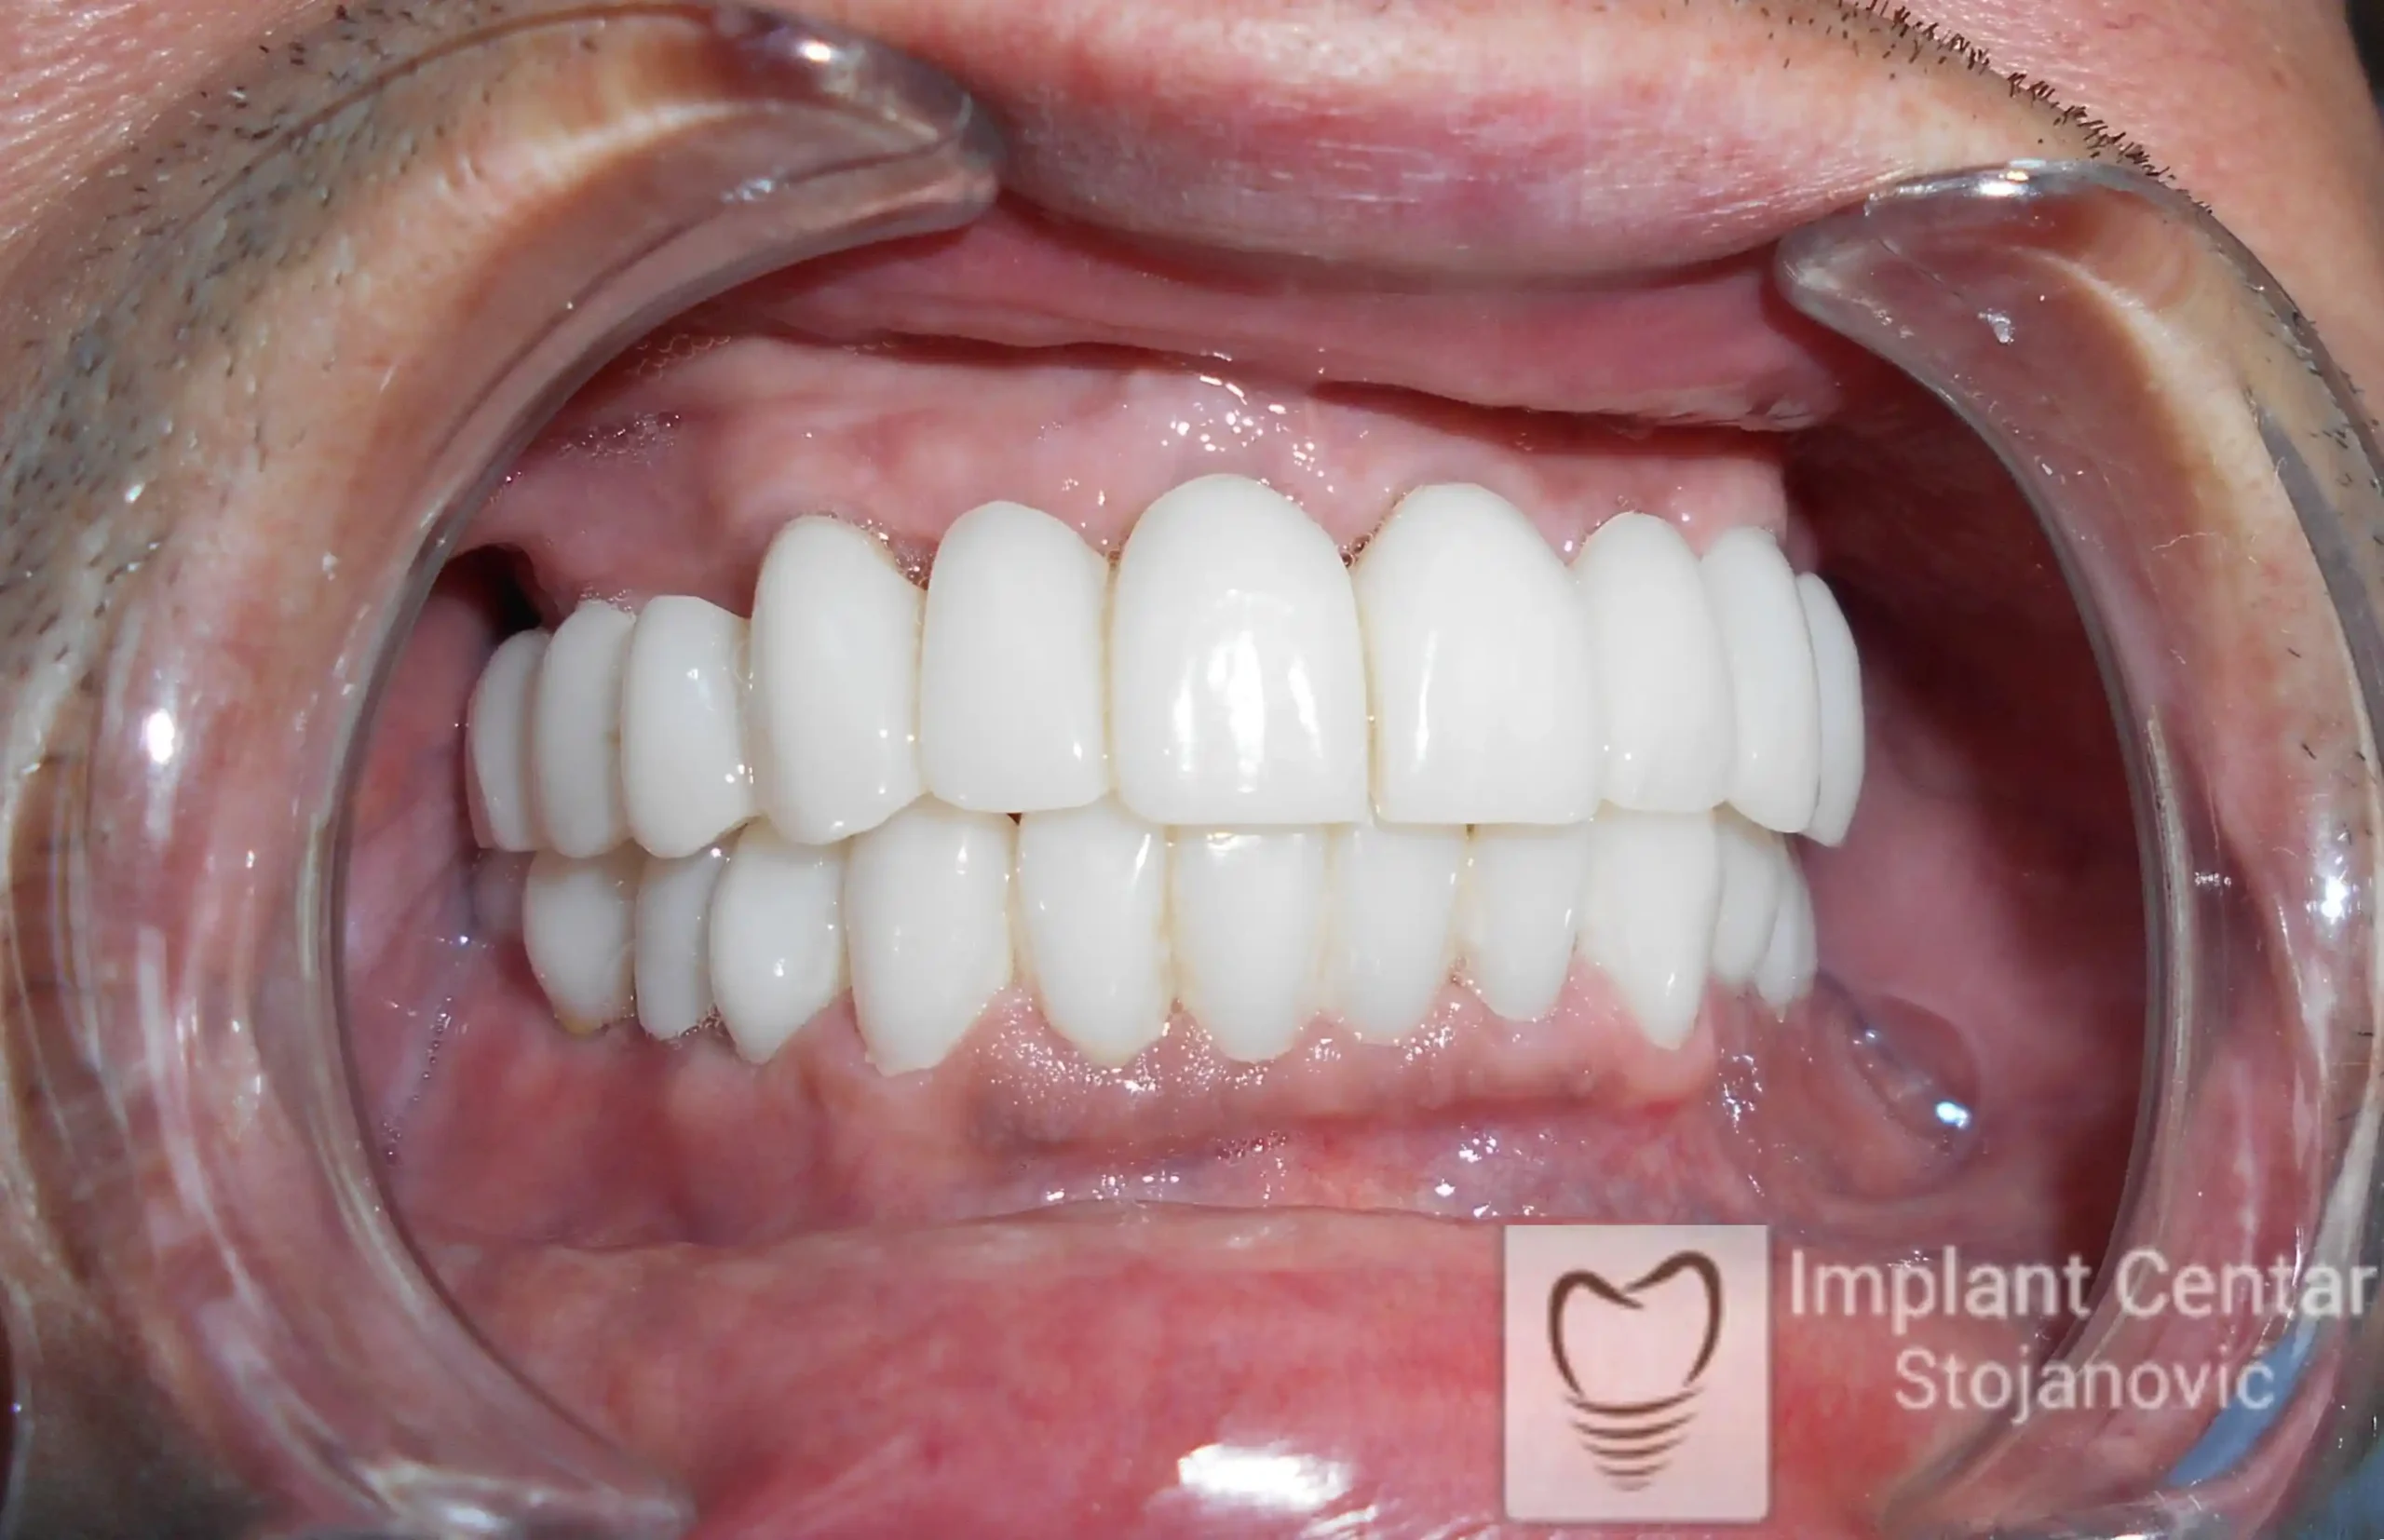

Tokom perioda oseointegracije, pacijent je bio zbrinut fiksnim privremenim krunicama, čime je već pet dana nakon intervencije obezbeđena potpuna funkcionalna i estetska rehabilitacija. Nakon završetka perioda integracije implantata, izrađeni su definitivni cirkonijum-keramički mostovi na implantatima.

Pacijent je izuzetno zadovoljan postignutim rezultatom, navodeći da po prvi put jasno oseća svoje nepce tokom žvakanja, kao i da se smeje sa punim samopouzdanjem.